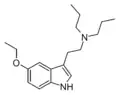

| Chemical structure | Short Name | Origin | Ring Substitution | RN1 | RN2 | Full Name | CAS Number |

|---|---|---|---|---|---|---|---|

| DET | artificial | H | CH2CH3 | CH2CH3 | N,N-diethyltryptamine | 61-51-8 |

| EPT | artificial | H | CH2CH3 | CH2CH2CH3 | N-Ethyl-N-propyltryptamine | 850032-68-7 |

| EiPT | artificial | H | CH2CH3 | CH(CH3)2 | N-Ethyl-N-isopropyltryptamine | 848130-11-0 |

| DPT | artificial | H | CH2CH2CH3 | CH2CH2CH3 | N,N-dipropyltryptamine | 61-52-9 |

| PiPT | artificial | H | CH2CH2CH3 | CH(CH3)2 | N-Propyl-N-isopropyltryptamine | 1354632-00-0 |

| DiPT | artificial | H | CH(CH3)2 | CH(CH3)2 | N,N-diisopropyltryptamine | 14780-24-6 |